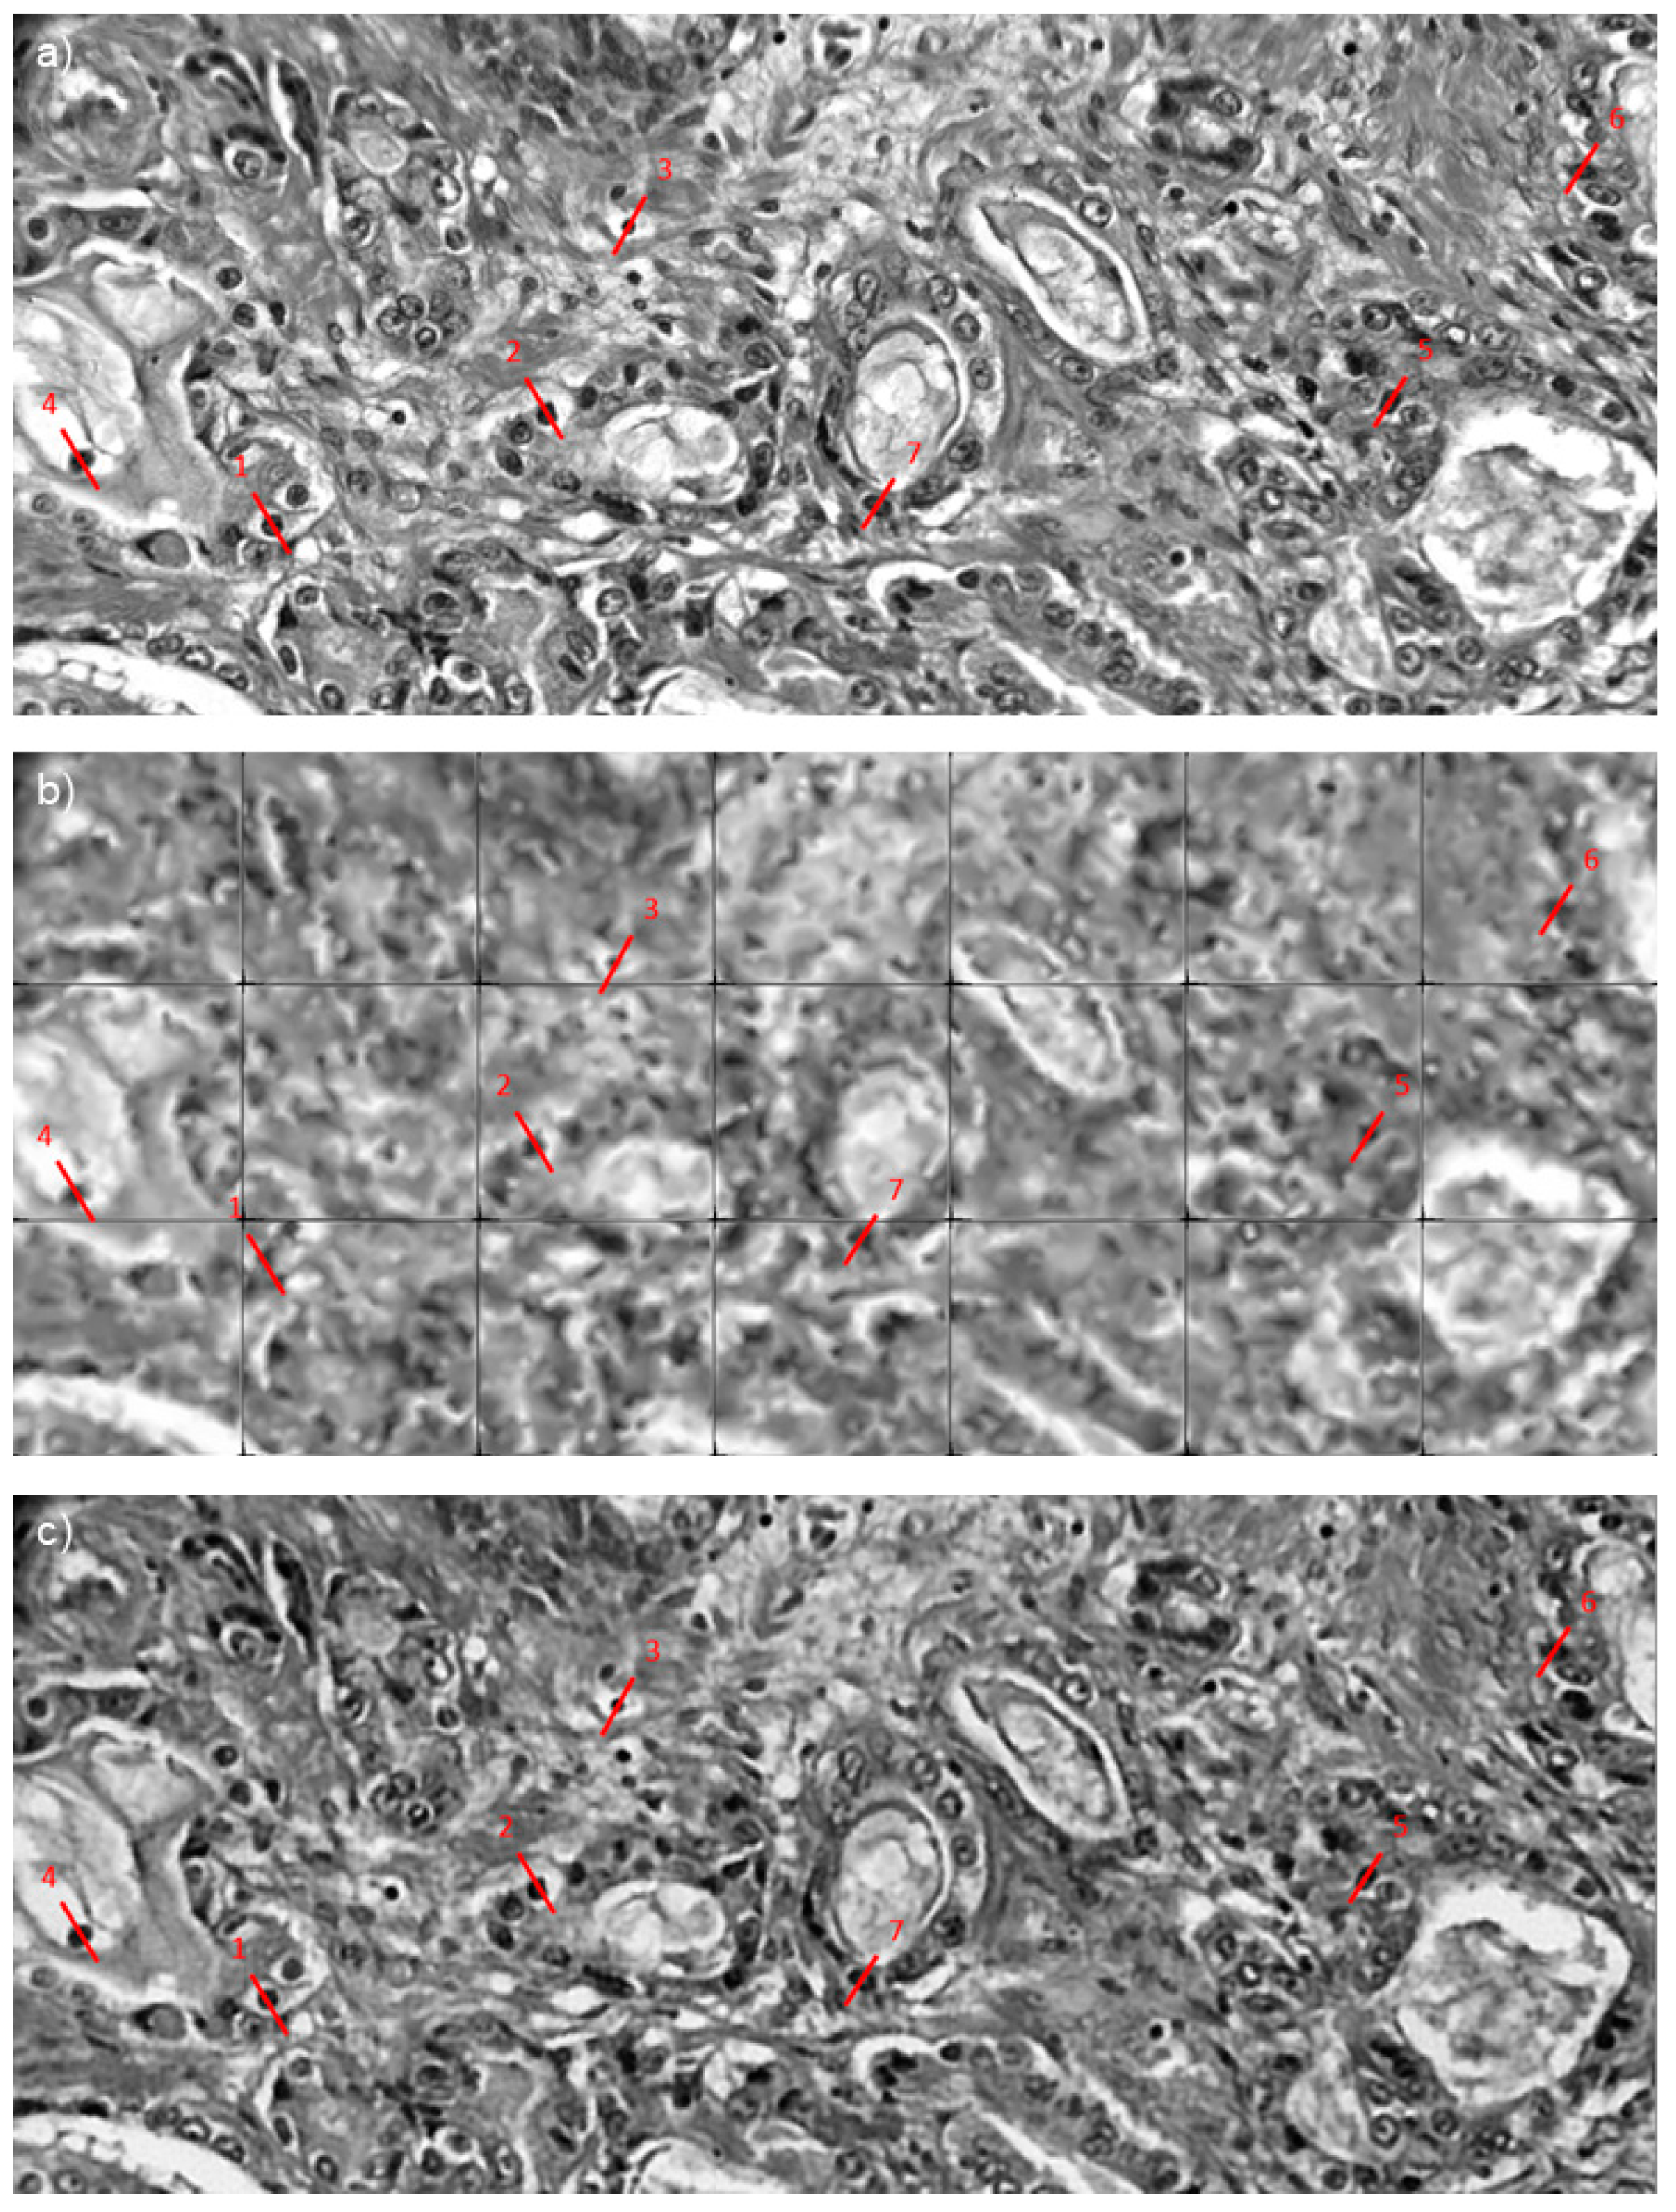

Figure 5a presents the ground truth images as taken from the microscope setup. Figure 5b is a synthetic recreation of the same scene as imaged using a fiber bundle. Figure 5c–f shows the reconstruction of the fiber image using Gaussian blurring, Linear interpolation, single-image autoencoder, and our proposed multi-frame auto-encoder, respectively. Red arrows have been drawn on each of the images to direct attention towards a small cell nucleus that is difficult to identify in most cases except MFAE.

Analysis shows that the SSIM is increased from an average of 32% in SIAE to 83% in MFAE (Table 1), and features appear better defined, as indicated by the red arrow in Figure 5. Having multiple rotated images to perform MFSR was not only capable of removing the honeycomb effect and restoring the information hidden by the cladding, but also the mean SSIM of fiber bundle images improved by 1.97-fold compared with the linear interpolation method on a single-image. Further work could improve the quality of the images but would require a much more complex architecture. From 420 testing images, the PSNR and SSIM were computed for each image (Table 1). When compared with similar attempts in multi-frame endomicroscopy, our method is the fastest (30 ms vs. ~1 s for [15,17]) with a higher SSIM and comparable PSNR.

To obtain an improved representation of the tissue post-reconstruction, the testing images were stitched together (Figure 6). Figure 6a is the original ground truth image. Figure 6b has been reconstructed using linear interpolation. This method is not accurate as the borders of each section are missing due to the nature of linear interpolation. Lastly, Figure 6c shows the multi-frame super-resolution images. Red lines indicate the cell nuclei to be measured and compared; this helps determine the accuracy of super-resolved shapes. All measurements were taken across the same area.

Figure 5. Reconstruction method comparison on acquired prostate images. (a) ground truth. (b) averaged fiber bundle. (c) gaussian blurring. (d) linear interpolation. (e) single-image autoencoder. (f) multi-frame autoencoder. Red arrows point to specific cell nuclei location across each image.

Figure 6. SR reconstruction of slices taken from images prostate tissue (cancer and non-cancer) slide. (a) ground truth image. (b) Linear interpolation. (c) MFAE. Red lines represent line profile taken of cell nuclei, line numbering is equivalent to cell numbers in Table 2.